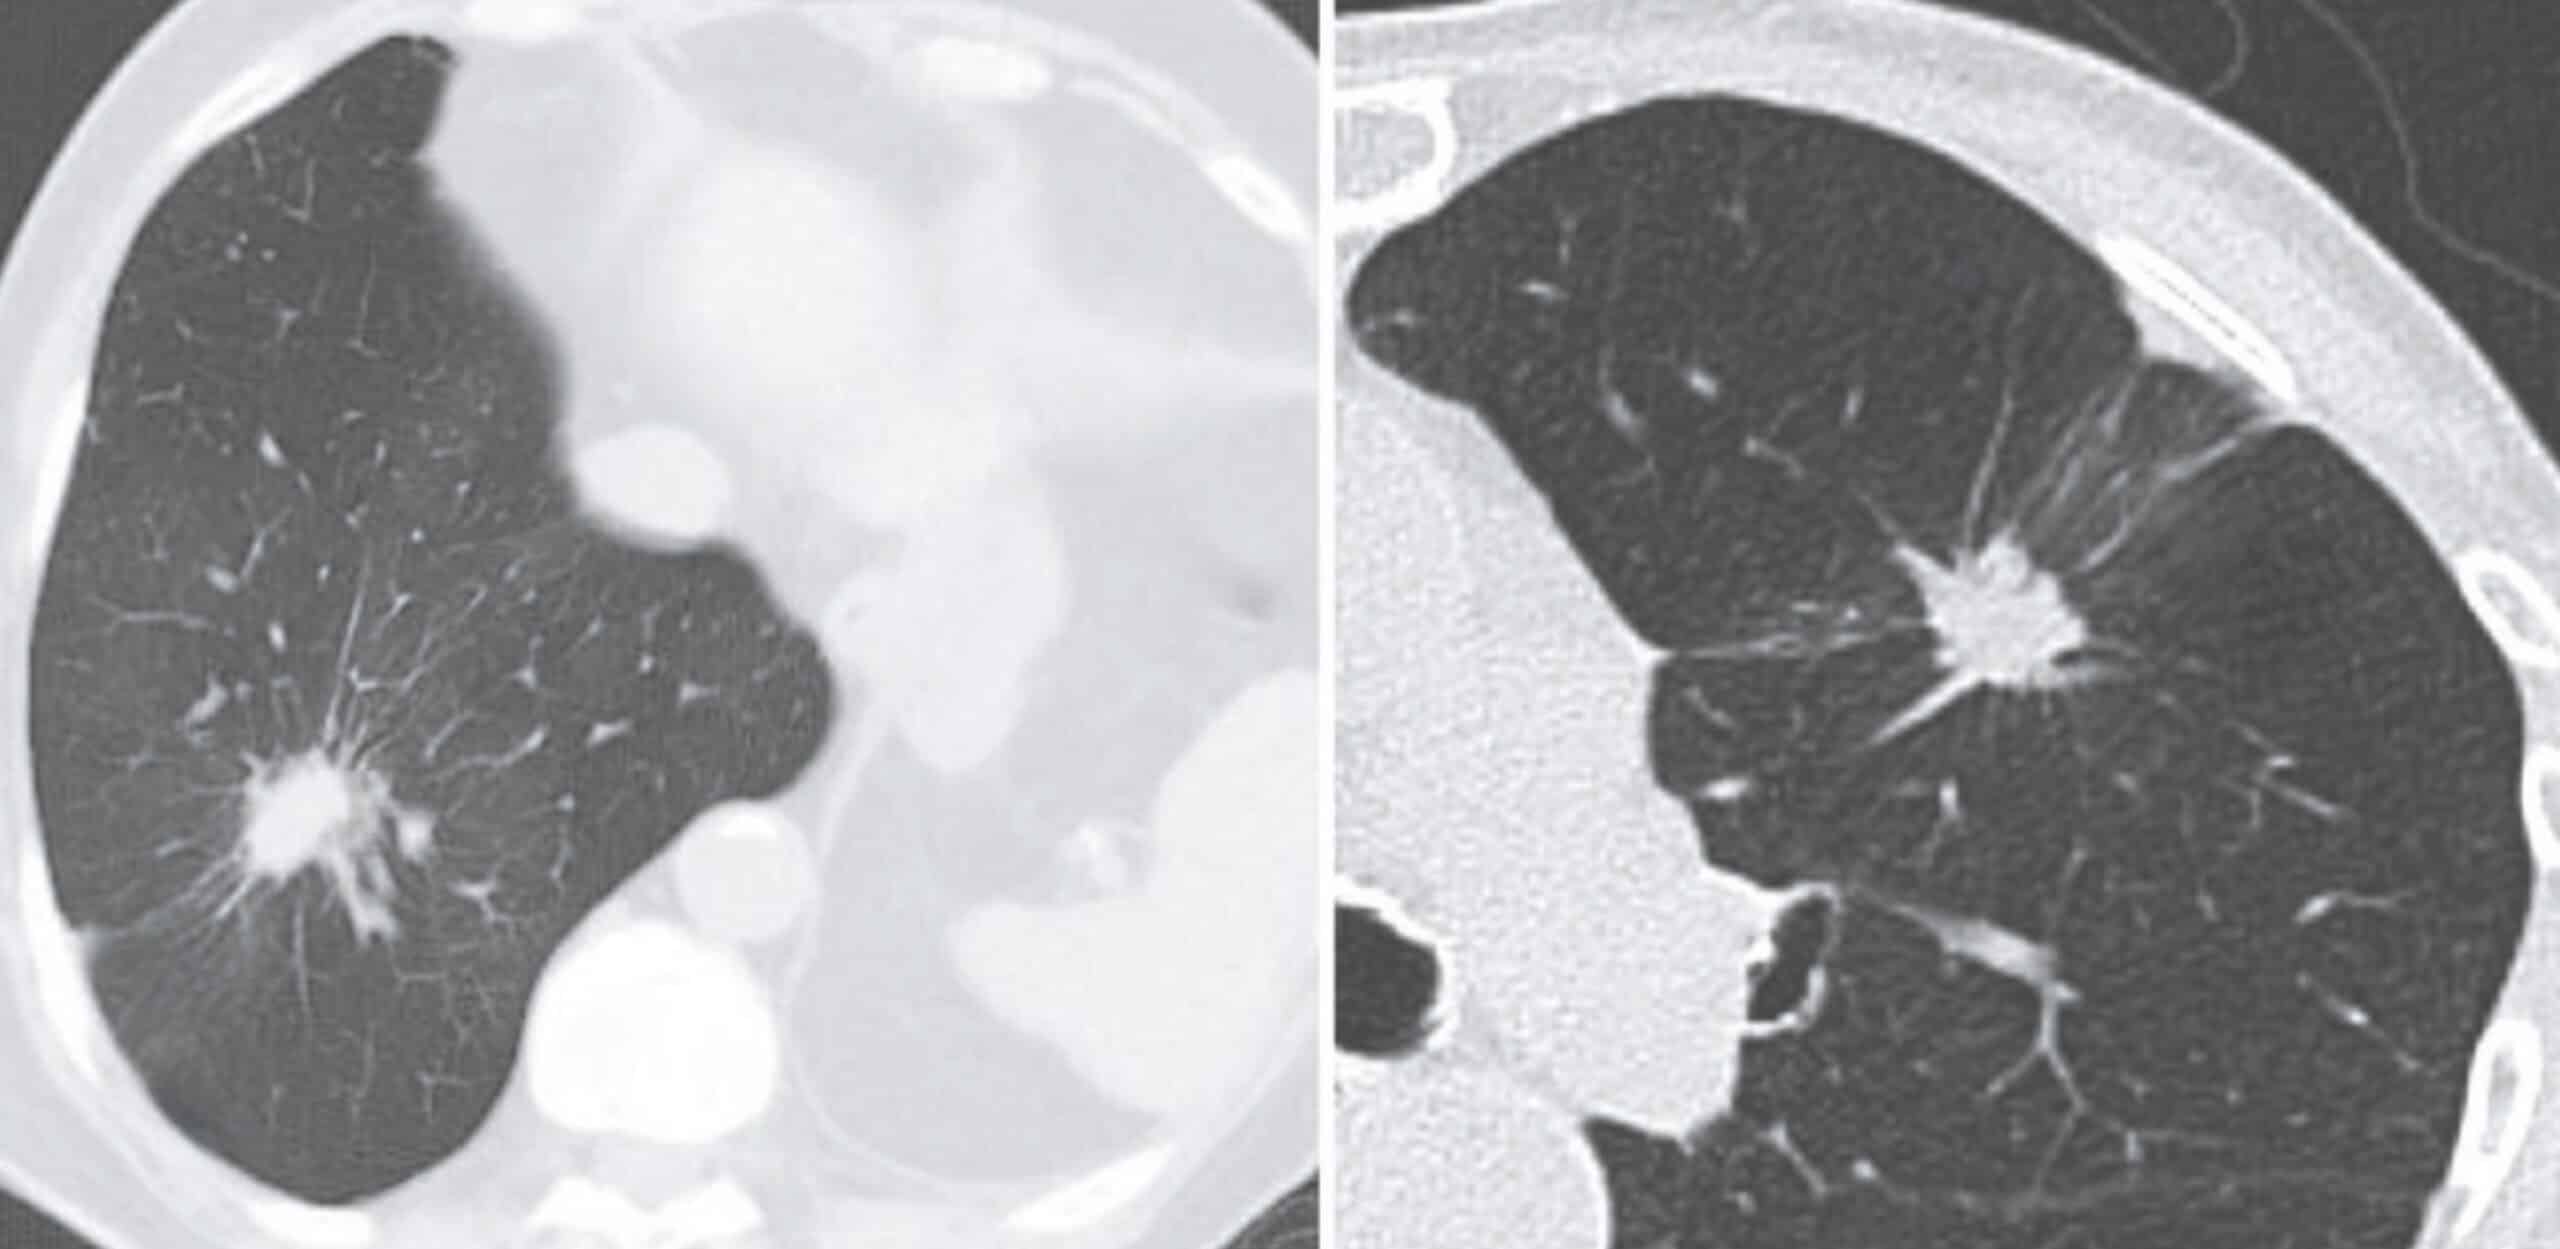

pleural surface without interruption, and forming a wedgeshaped protrusion on the visceral pleura

Right: The presence of two lines running from the lesion to

the visceral pleura (or even more) is called rabbit ears. Yudin 2023